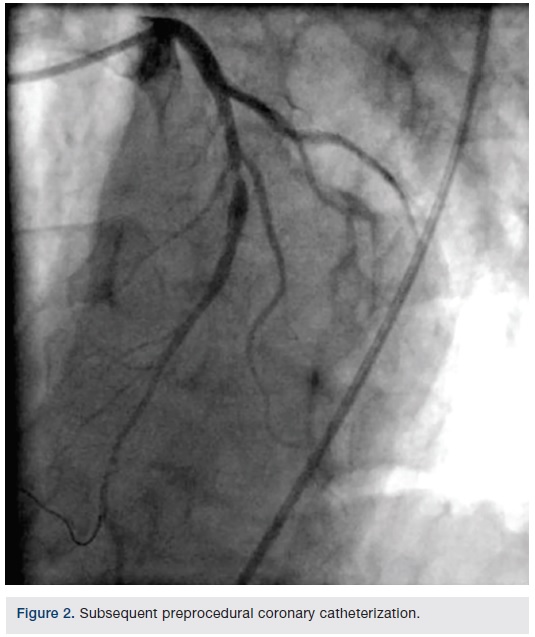

The SOMATOM Force CT system (Siemens Healthcare), which enables fast temporal resolution, was used to perform a coronary CT angiogram (CCTA) on an emergency department patient. The CCTA displayed a 90 percent or greater non-calcified short stenosis in the mid left anterior descending coronary artery (LAD). The next day, the patient’s coronary catheterization revealed a mid-LAD stenosis, type B1 and ulcerative, just distal to a moderate-sized diagonal. A drug-eluting stent was placed; no residual stenosis and normal distal flow was observed. A day after stent placement, the patient was discharged.

Images/courtesy St. Elizabeth Hospital, Edgewood, Kentucky